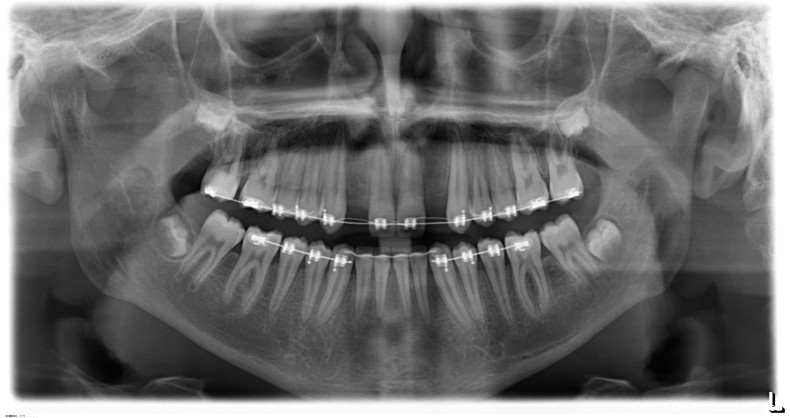

Ein 14-jähriger Patient wurde bei Aplasie der beiden oberen seitlichen Schneidezähne mit dem Ziel der beidseitigen Lückenöffnung kieferorthopädisch therapiert (Abb. 1a+b). Zum Ende der kieferorthopädischen Behandlung wurden zwei Miniimplantate in Regio 2er als temporärer Zahnersatz inseriert (Benefit System, PSM, 2 x 13 mm, Abb. 2a+b). Nach Abdrucknahme wurden Kronen auf den Peek-Abutments modelliert und diese mit Kunststoff auf die Abutments geklebt (Abb. 3a–d). In den Abbildungen 3 und 4 sind die klinischen und röntgenologischen Nachkontrollen innerhalb der nächsten achteinhalb Jahre dokumentiert. Man erkennt einen sowohl in der Höhe als auch in bukkopalatinalen Breite verbleibenden gesunden Knochen ohne Anzeichen einer Atrophie. Im Alter von 23 Jahren wurden die definitiven Implantate ohne die Notwendigkeit einer Augmentation eingesetzt (Abb. 5) und nach Einheilung prothetisch versorgt (Abb. 6a–e und Abb. 7a–c).

Nach Abschluss der kieferorthopädischen Pfeilerverteilung wurden zwei Miniimplantate in Regio 3er inseriert (2 x 13 mm). Nach Herstellung im Labor wurden Kronen auf den Miniimplantaten aufgeschraubt (Abb. 13+16a–d). Auch hier wurde darauf geachtet, dass die Kronen aus der Okklusion geschliffen wurden (Abb. 14). Bei den Nachkontrollen zeigten sich ebenfalls stabile Miniimplantate und ein entzündungsfreies Implantatlager ohne erkennbare Atrophie des Knochens (Abb. 15 und 16a–d).